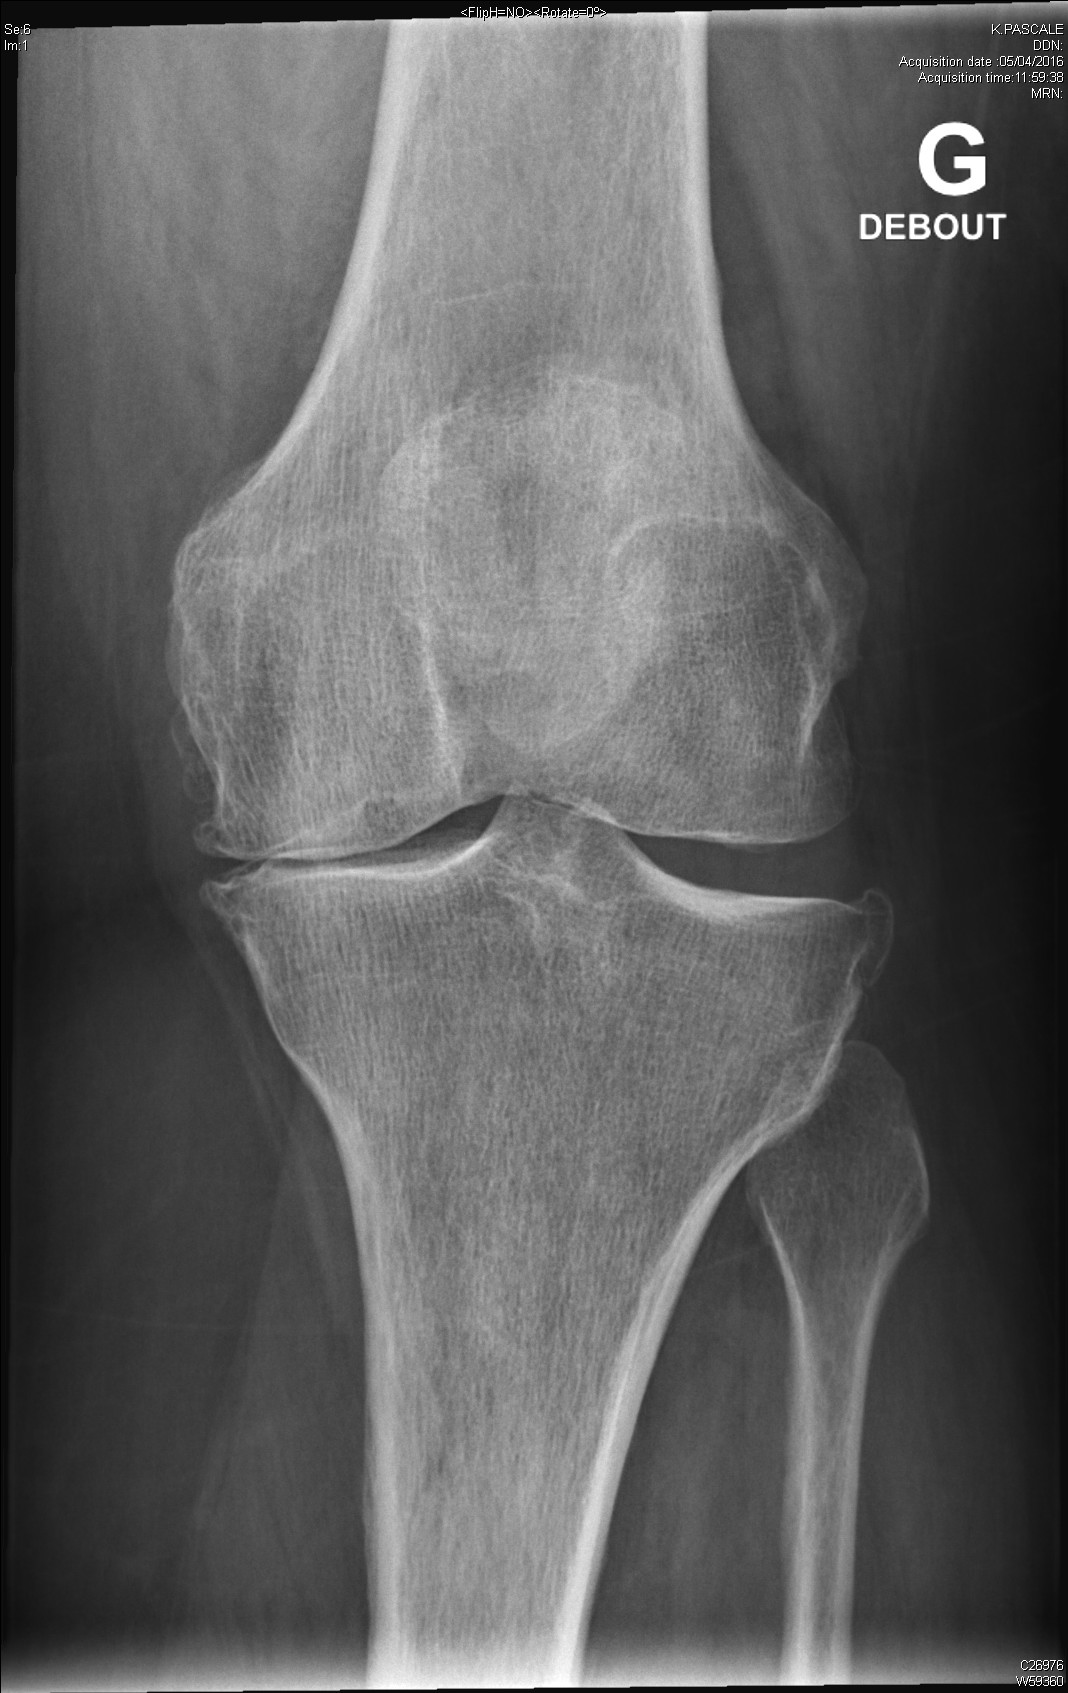

arthrite destructrice évoluée du genou dans le cadre d'une polyarthrite rhumatoïde

Chondrocalcinose articulaire typique

Gonarthrose évoluée sur terrain d'obésité